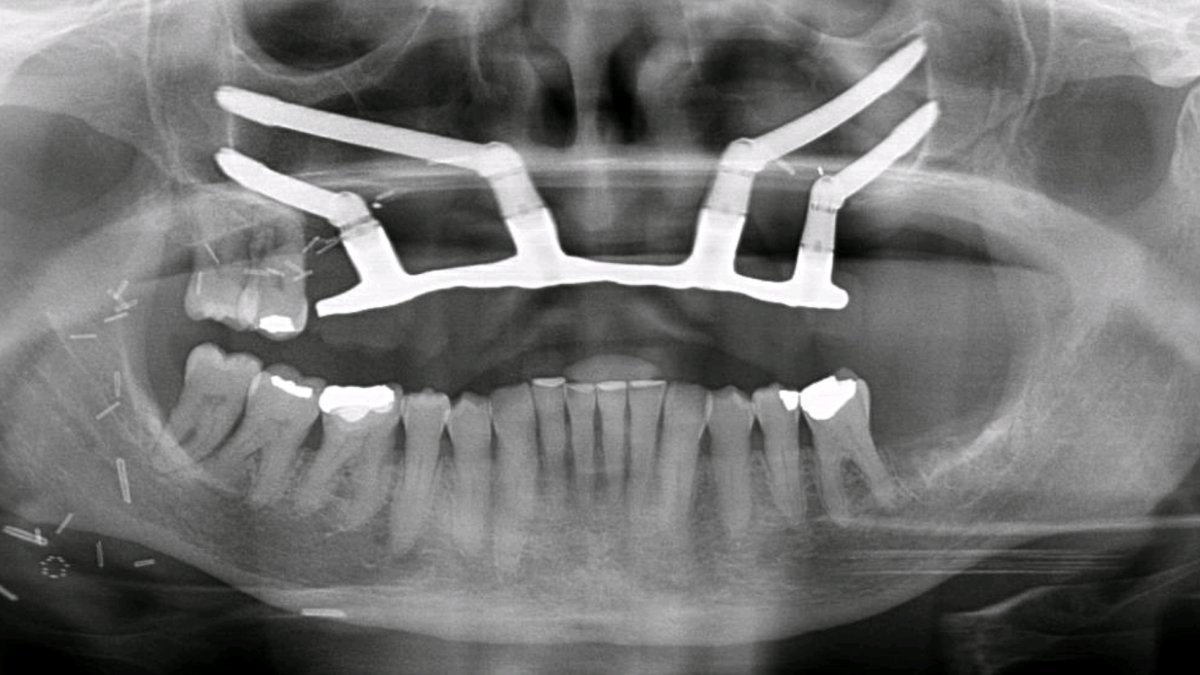

Post-op Radiograph